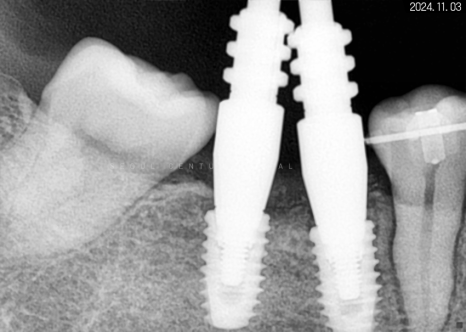

따라서 적정 시기에

CT를 촬영해 치조골 폭과 밀도를

철저하게 분석한 다음 정확한 자리를 선정하고

임플란트 식립을 진행했습니다.

하악 좌측 사랑니 발거 후

임플란트가 필요한 부분들에

픽스처를 견고하게 식립해 드렸습니다.

*기다란 막대기는 뿌리 끝 길이를

측정하기 위해 사용한 도구입니다.